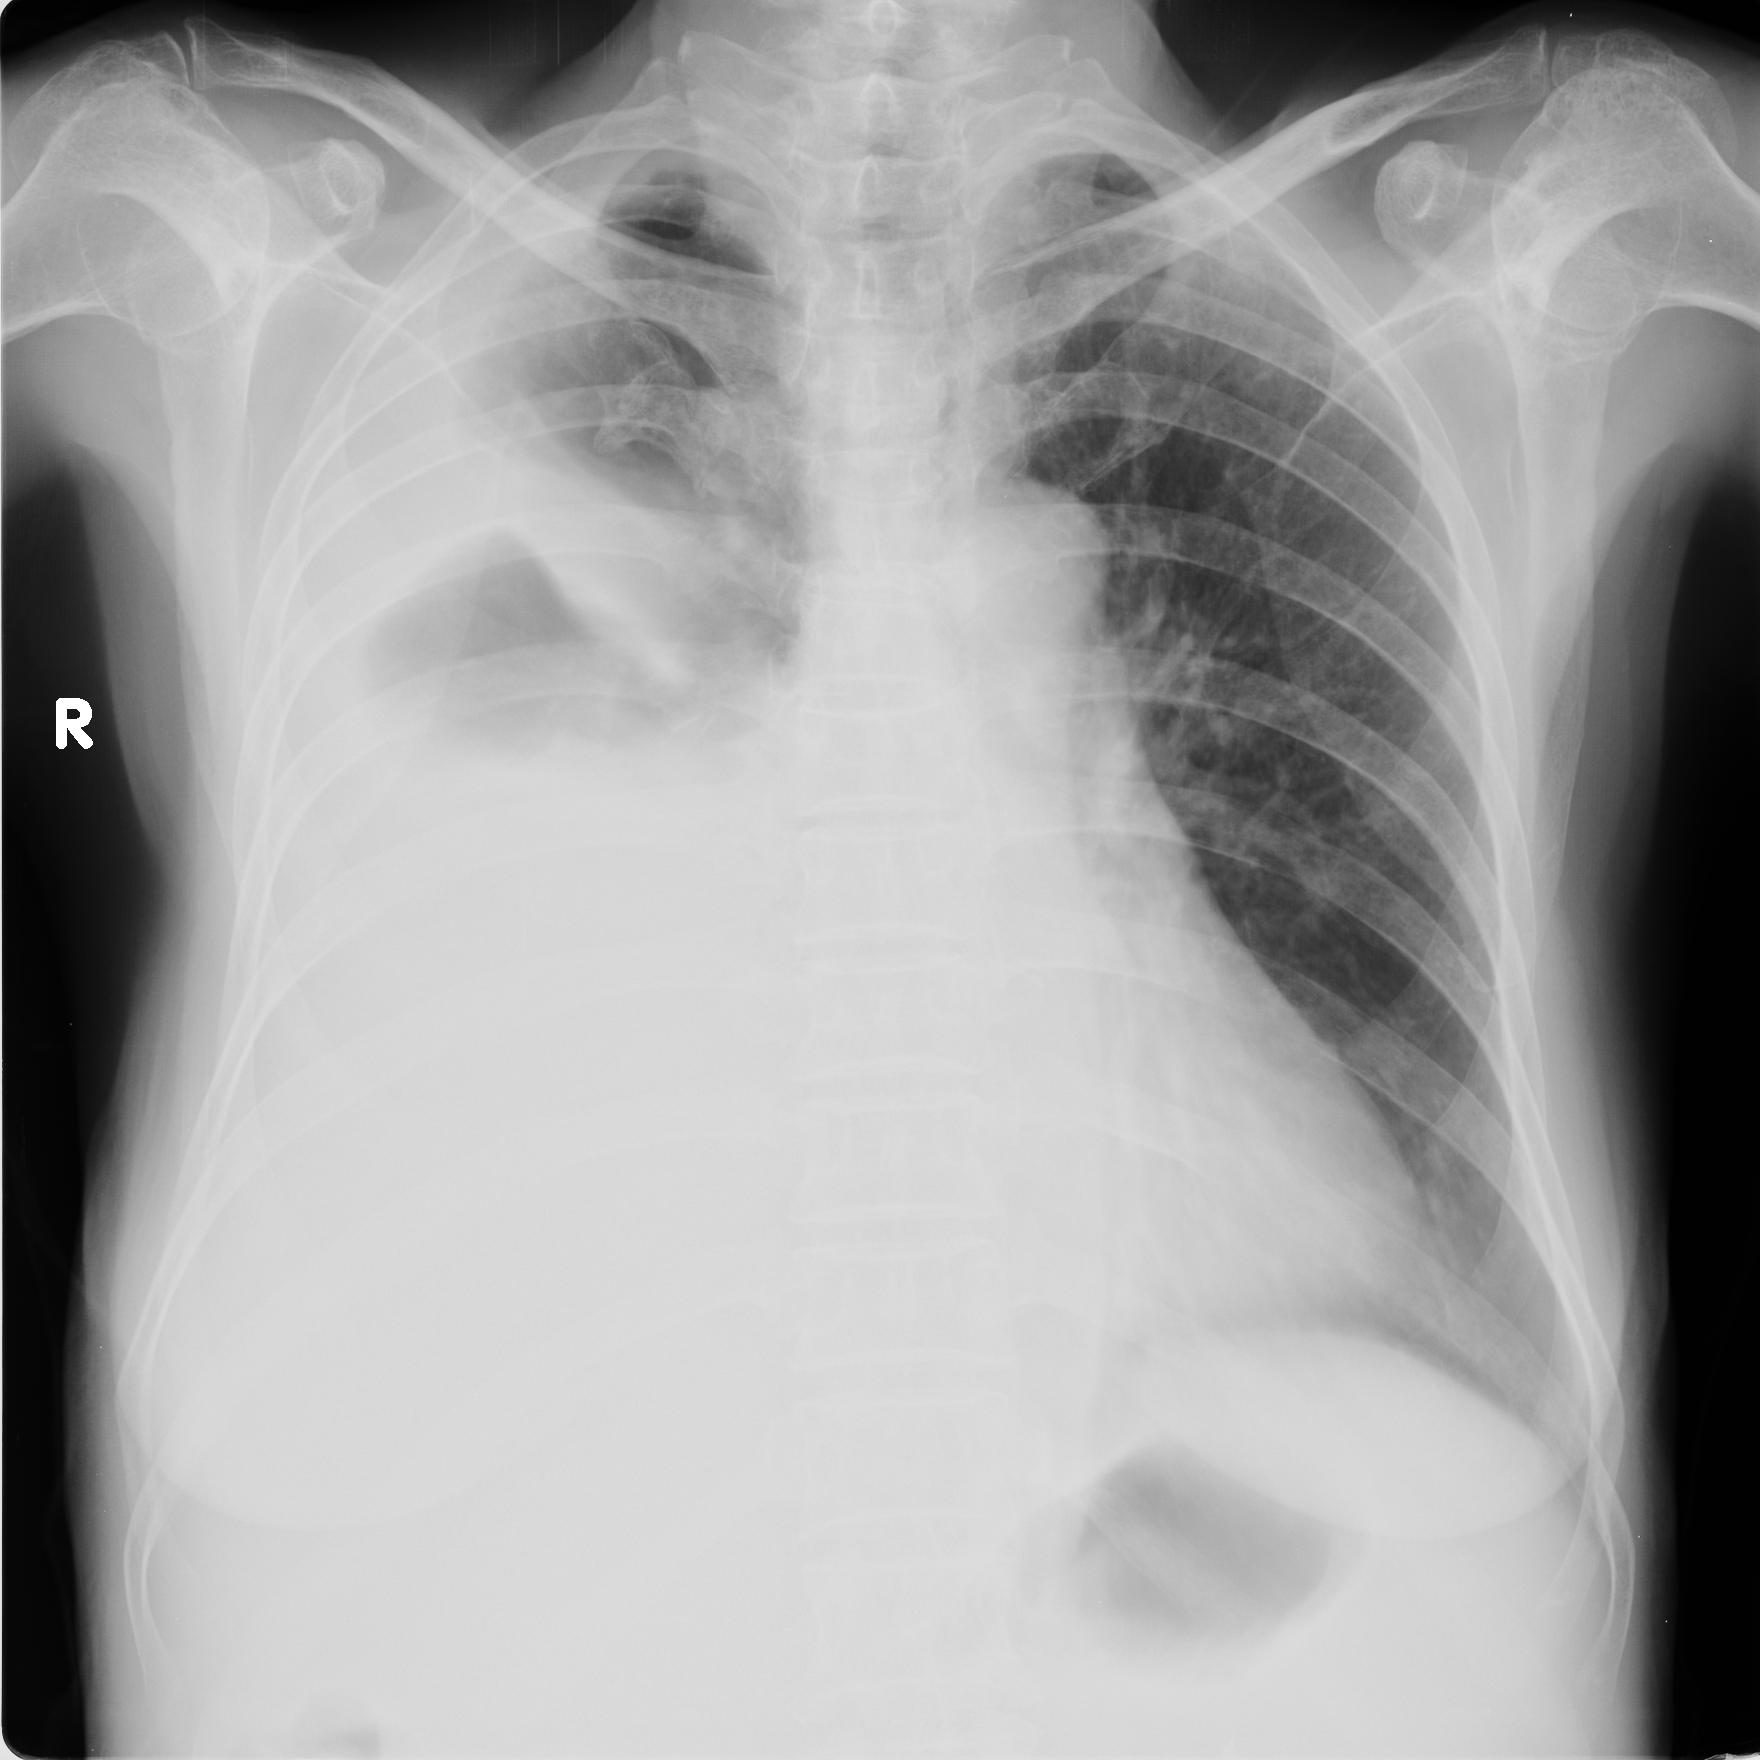

以下是引用zhangzhongshou在2008-5-24 13:39:00的发言:[br]小红右侧大量胸腔积液,右侧中叶台阶征/水平叶裂积液/右上肺纤维灶不除外,建议侧位片,必要时进一步检查。[br]小明:左上肺结核瘤可能性大,请结合临床,必要时建议ct检查。[br][br]影像诊断必须要密切结合临床,建议楼主以后不要上传这样的看图说话。谢谢了!

以下是引用黑白光影在2008-5-24 15:32:00的发言:[br]看图不说话对不起观众,下面开始乱说:[br]老红右侧大量胸腔积液,部分肺膨胀不全。[br]老明左上肺癌可能。